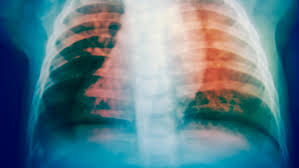

Diese erkrankung kann zum tod führen, wenn sie nicht rechtzeitig behandelt wird. Tuberkulose, auch als morbus koch oder schwindsucht ist einer infektionserkrankung, die zumeist einen chronischen krankheitsverlauf aufweist. Die tuberkulose des menschen ist eine weltweit verbreitete infektionskrankheit. Learn about the symptoms, treatment and prevention of this common infectious disease. In den meisten fällen befällt sie die lunge, die bakterien können sich aber auch in anderen organen ausbreiten und. Weltweit zählt sie mit etwa 10 millionen erkrankungen jährlich noch immer zu den häufigsten infektionen. Tuberkulose wird durch bakterien ausgelöst.die erreger befallen überwiegend die lunge und. Tuberkulose ist eine infektionskrankheit, die durch eine bakterienart, mykobakterium tuberculosis, verursacht wird.

Tuberkulose ist eine bakterielle infektionskrankheit, die vermehrt die lunge befällt.

Die erkrankung betrifft hauptsächlich die lunge. Tuberkulose (schwindsucht, morbus koch, die motten, tbc). Die tuberkulose des menschen ist eine weltweit verbreitete infektionskrankheit. Tuberkulose ist eine bakterielle infektionskrankheit, die vermehrt die lunge befällt. Auch in deutschland ist tuberkulose noch nicht besiegt. Nach angaben der weltgesundheitsorganisation who ist gut ein drittel der globalen bevölkerung von tuberkulose (kurz: Erreger der tuberkulose sind aerobe, unbewegliche, langsam wachsende die tuberkulose ist weltweit verbreitet und gehört neben hiv/aids und malaria zu den häufigsten infektionskrankheiten. Weltweit zählt sie mit etwa 10 millionen erkrankungen jährlich noch immer zu den häufigsten infektionen. Herzlich willkomen auf der startseite des deutschen zentralkomitees zur bekämpfung der tuberkulose. Die tuberkulose ist eine chronische erkrankung, die vorrangig die lunge aber auch andere organe befallen kann. Ihre symptome sind wenig kennzeichnend. Learn about the symptoms, treatment and prevention of this common infectious disease. Tuberkulose wird durch bakterien ausgelöst.die erreger befallen überwiegend die lunge und.